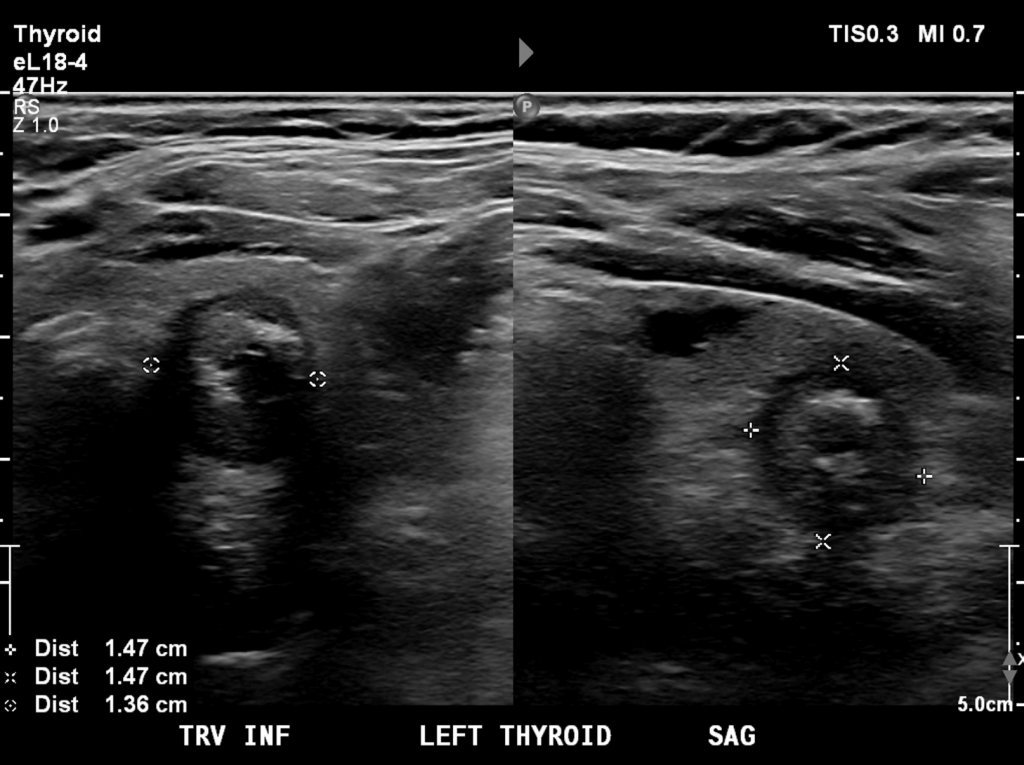

During my third-year surgical rotation, I co-authored a case report describing a rare overlap of two common endocrine conditions: a parathyroid adenoma and papillary thyroid carcinoma. Our patient presented with primary hyperparathyroidism and hypercalcemia, but surgical pathology revealed something unexpected: the thyroid cancer had actually invaded the parathyroid adenoma itself

This unusual histologic interplay complicates what is usually a straightforward operation and highlights the importance of thorough preoperative imaging, intraoperative vigilance, and careful pathology review. Cases like this remind me that in medicine, just as in research, it’s often the rare or unexpected findings that sharpen our skills and shape better patient care.